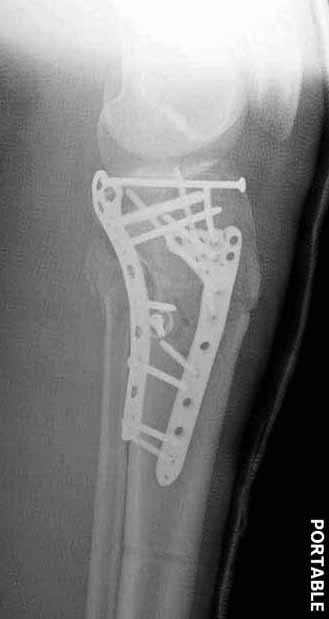

В приложении этапы фиксации Both Column Fx и пластиной Synthes для плеча при переломе медиального мыщелка.

Был бы очень признателен Александру Челнокову за предоставление методички..... Коллеги, спасибо за советы... К сожалению томографа в больнице нет. Рассматривали вариант штифтования данного перелома, но большинство коллег против, да и опыта штифтования подобных переломов тоже нет. Если есть рентгенограммы заштифтованных подобных переломов, коллеги, выложите на обозрение, пожалуйста….Долго искали и все же остановили пока свой выбор на проксимальной медиальной большеберцовой пластине Numelock фирмы Страйкер.